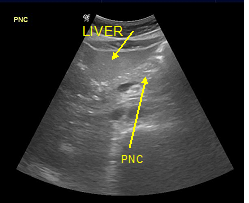

In a 4-years period (from 2016 to 2019) a retrospective study of 887 patients with fatty infiltration of the liver was performed, out of which 608 were males and 272 were females, aged 42 to 69 and 7 obese children (age from 8 to 13 years). All patients were examined in the ultrasound cabinet of our hospital (hospitalized, regular appointments and emergency incidents) and subjected to upper abdominal ultrasound scan, with convex transducer 4C MHz, in three ultrasound imaging planes: transverse, oblique and sagittal planes.5−7 In order to better depict the liver, especially in obese patients or those with excessive intestinal gas, the patients were asked to inhale deeply and hold their breath for the duration of the ultrasonographic examination for a few seconds at a time, so that the liver could be visible in its entirety. The ultrasound examination revealed the echogenicity of the parenchyma of the liver and was compared with the parenchyma of the right kidney, the spleen and the pancreas (Figure 1−3). Τhere is always the risk of missing a diagnosis of mild hepatic steatosis on ultrasound if there is concurrent chronic renal disease, which increases the echogenicity of the kidneys (Figure 4), if there is any doubt that the patient might have a chronic renal disease, comparison of the liver to the left kidney and the spleen may be useful.8

Figure 1 Right renal cortex appearing hypoechoic compared to the liver parenchyma.

The fatty infiltration of the liver is shown on ultrasound with significantly increased echogenicity "bright liver", in comparison with the right kidney cortex (Figure 1). Normally, the liver and the renal cortex have similar echogenicity, relative to the parenchyma of the pancreas and the spleen. The maximum diameter of the liver in the midclavicular line (MCL) was increased, right lobe>15 cm (Figure 5). Also significant features are the absence of mass effect on intrahepatic vasculature (Figure 6) as well as the poor visualization of the deep parts of the liver (Figure 7), due to decreased permeability of the acoustic beam. A focal or diffuse morphology has been shown to increase the echogenicity of the fatty liver. Differential diagnosis is caused by focal fat infiltration (Figure 8), which has a geographic distribution. In this case, hypoechoic areas correspond to normal hepatic parenchyma on fatty infiltration sites, whereas, normal parenchyma islets can easily be identified due to their typical positions, in front of the right branch of the portal vein, its division, around the area of the gallbladder and the caudate lobe.9−13